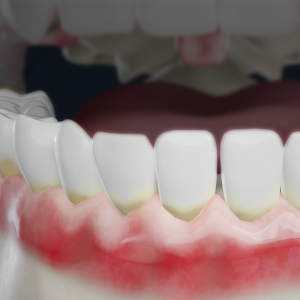

If you’ve been told you need a “deep cleaning,” you might be feeling a little unsure…But rest assured, a deep